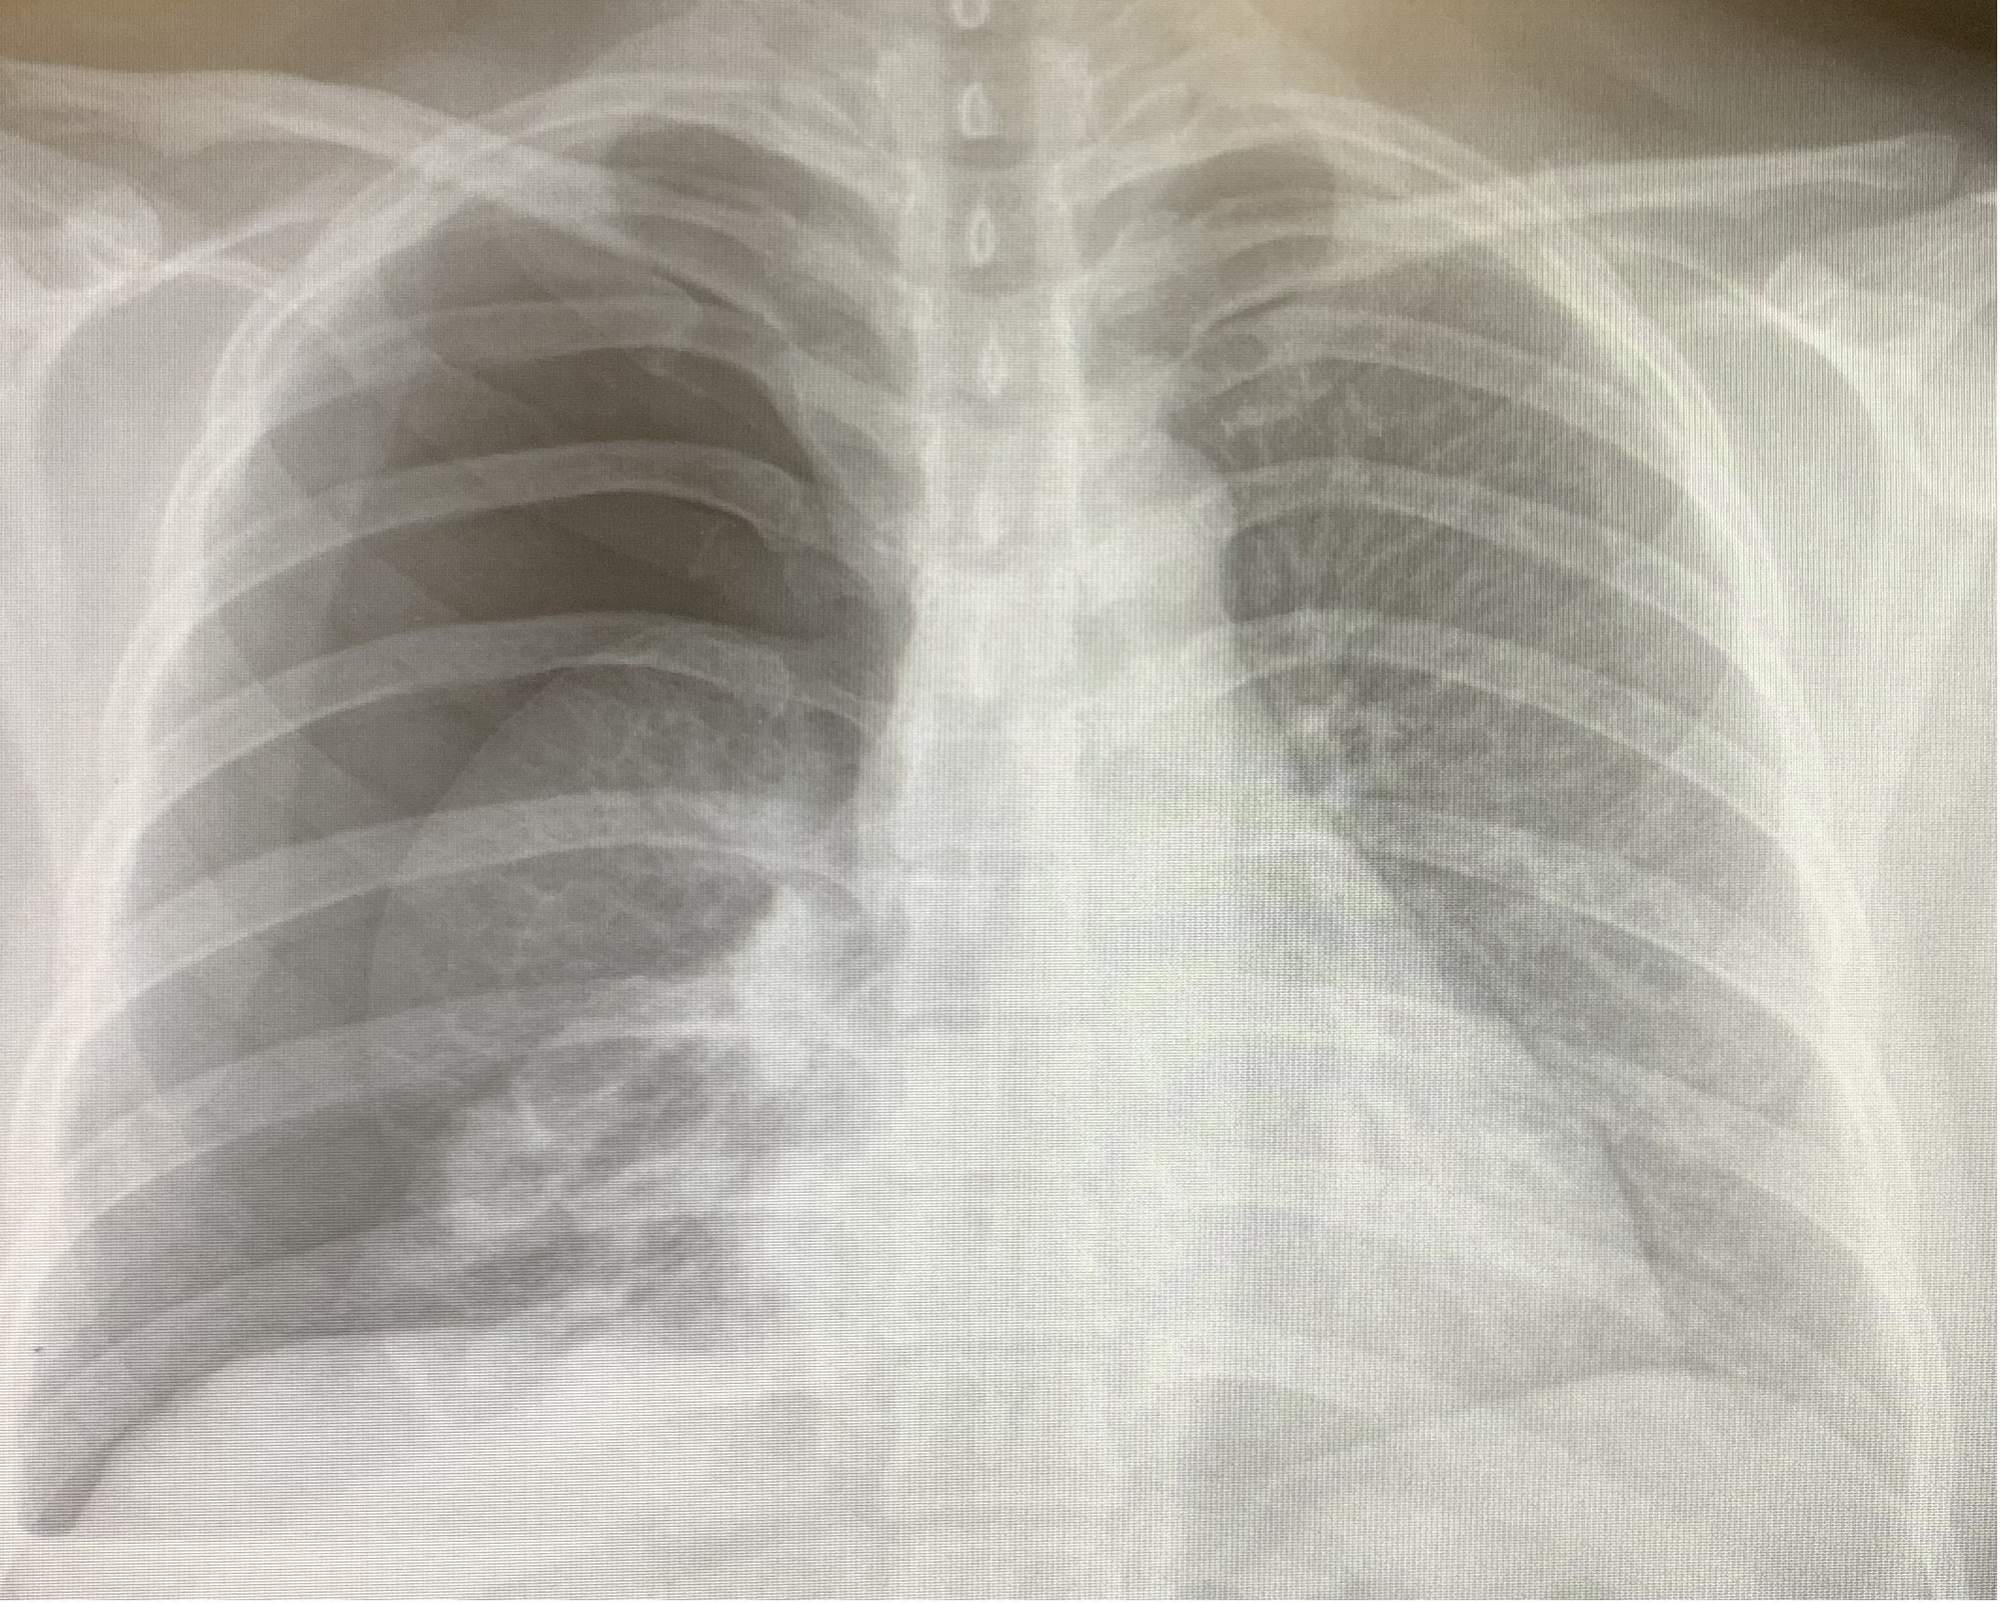

这位患者因胸闷、胸痛7小时入院,胸部CT检查示“右侧气胸,右肺压缩约80%”,既往身体健康状况良好,无传染病或慢性病,无气胸发作史。急诊行右侧胸腔闭式引流排气,术后第2天复查胸片气胸好转,肺膨胀好,见右下肺阴影。完善胸部CT增强发现 右肺下叶外基底段可见一肿块样状实变密度影,边界尚清,边缘不光整,呈分叶状改变,并牵拉邻近胸膜,较大截面约为41mm×30mm,其内支气管截断,平扫CT值约为28Hu,增强扫描病变中央见片状不强化区,边缘呈渐进性强化,CT值分别为52Hu、64Hu、75Hu;病变旁可见一囊腔影,边界欠清,囊壁不规则,周围局部见磨玻璃密度影,较大截面约为37mm×23mm。考虑恶性肿瘤性病变可能性大。

图6:右侧气胸,右肺压缩约80%

患者在我的建议下接受手术治疗。行单孔胸腔镜右下肺叶切除,术中冰冻病理提示右下肺浸润型腺癌,行肺癌根治清扫纵隔淋巴结,术后病理纵隔淋巴结未见转移。术后恢复顺利,术后3天出院,这周来门诊复,诉有轻微的咳嗽及胸痛,可以耐受。还遇到了上面那位左下肺肺癌患者,还互相加了微信,互相鼓励,一起走在抗癌的道路上。复查胸片肺膨胀好。术后病理右下肺浸润性腺癌伴坏死,实性型约占50%、腺泡型约占50%,肿物最大径约6cm,,术后病理诊断pT3N0M0 IIB期。按照NCCN指南患者需要术后辅助治疗,行基因检测,如果发现EGFR敏感基因突变,可行奥希替尼辅助靶向治疗。如果无基因突变,建议以铂类为基础的方案进行辅助化疗。

图9:术后1周胸片